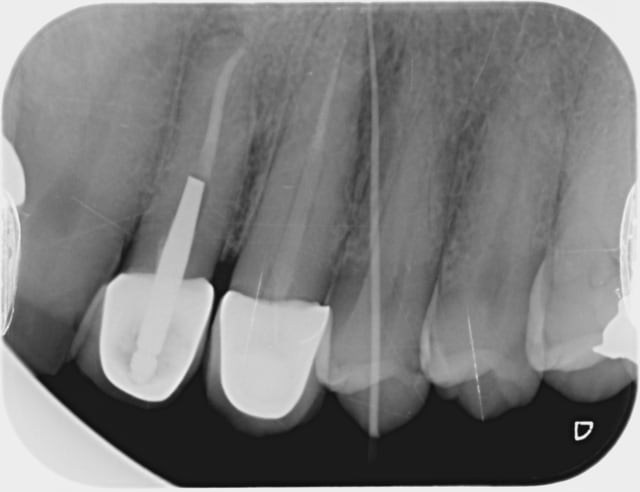

Bonjour je suis nouveau sur le forum , voilà je suis en 6 ème année , à peine mon cas fini pis j'ai une fistule (je crois que ça s'appelle comme ça) sur la dent du haut à gauche (je crois que c'est la gauche), que faire ?

T'es sûr que c'est pas plutôt une perforation, je crois que ça s'appelle comme ça, faite en faisant l'ouverture de chambre sur la 4 qui était saine (puis en alésant l'os comme un goret) mais qu'il aurait été bon de couronner pour faire du fric, je crois que ça s'appelle comme ça aussi ^^

Démontage 23 (ccm + tenon fibré), reprise du traitement canalaire et remontage/rebasage, dt prov sur 23, temporisation 3/6 mois, contrôle radio, si problème de sous (dt prov collée en définitif, sinon 23 à refaire...

Radio nulle, apex 23 !!!

ya rien sur la 24 !!!

roger chicot écrivait:

----------------------

> Démontage 23 (ccm + tenon fibré), reprise du traitement canalaire et

> remontage/rebasage, dt prov sur 23, temporisation 3/6 mois, contrôle radio, si

> problème de sous (dt prov collée en définitif, sinon 23 à refaire...

> Radio nulle, apex 23 !!!

> ya rien sur la 24 !!!

> Alapex est un troll !!!

Mais JE n'ai pas , ni voulu faire croire à un gutta dans la 24 ouverte à l'arrache , comme on le voit sur cette excellent photo , le cône rentre sans difficulté par la fistule jusqu'à moi en place de 23 ...)))

Espérons que le fibré est collé avec un ciment conventionnel ... ça serait nickel .